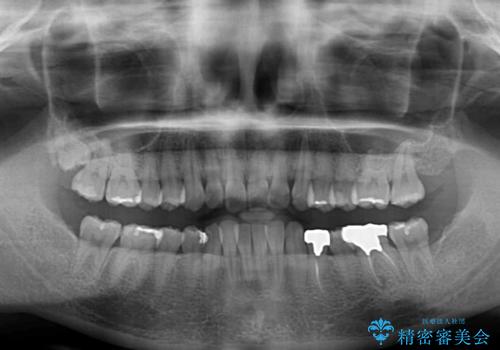

- 前歯のデコボコと深い咬み込みを気にして来院された患者様です。

インビザラインを用いて、前歯の叢生を解消するとともに、深い咬み合わせ(ディープバイト)を改善していくこととしました。

奥歯を後方に直立させることで深い咬み合わせを改善を図り、隠れていた下顎前歯が見えるほどになりました。